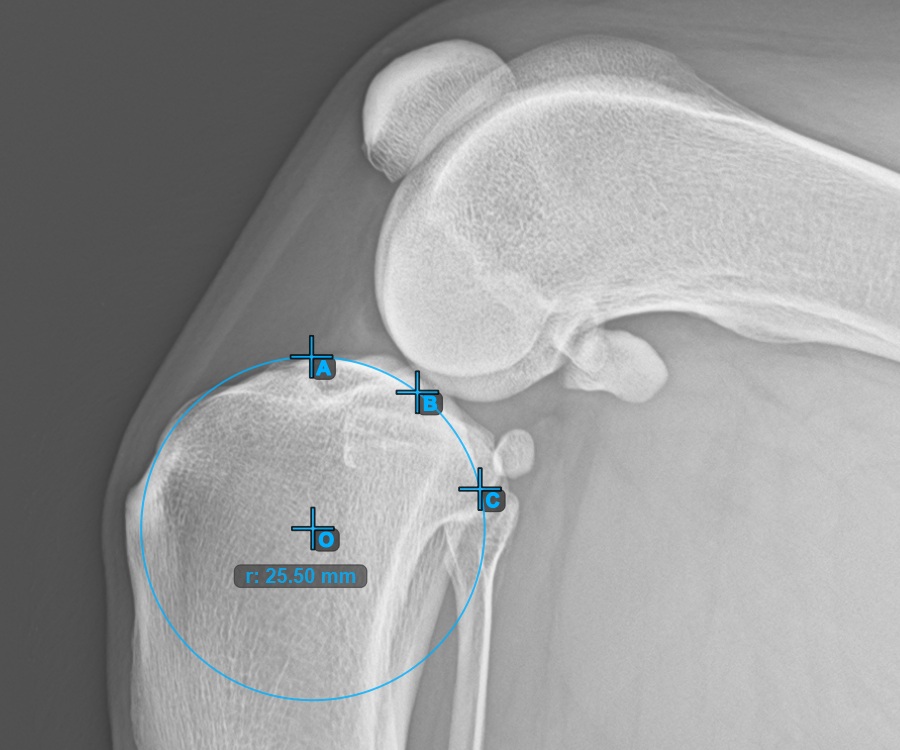

Starten Sie die Messung, indem Sie die drei Punkte am Condylus Medialis Tibialis markieren.

Markieren Sie die drei Punkte am Hauptkondylus des Tibiaknochens (Medialis Tibialis). Unabhängig von der Reihenfolge stellen Sie sicher, dass Sie den vordersten Punkt, den hintersten Punkt und den Mittelpunkt des Medialis Tibialis markieren. Basierend auf den drei gesetzten Punkten wird automatisch ein Kreis konstruiert.

Das Bild unten zeigt die typische Platzierung der drei Punkte am Condylus Medialis Tibialis.